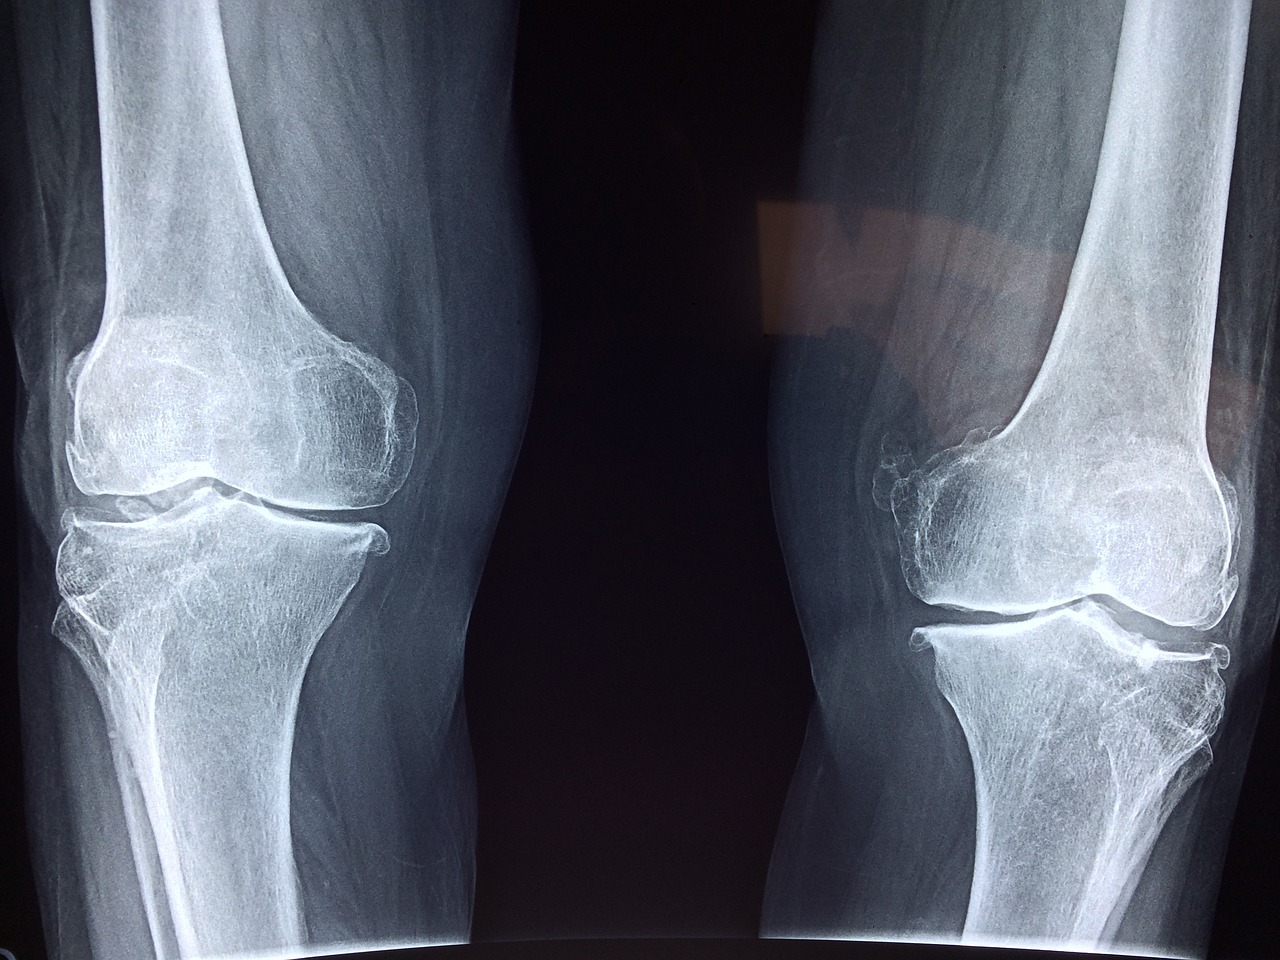

콘드로이친이 부족하면 연골이 뻣뻣해지고 쉽게 손상되어, 퇴행성 관절염으로 이어질 수 있습니다. 꾸준한 관리, 정말 중요하겠죠?!

골관절염 환자를 대상으로 한 연구에서, 콘드로이친 섭취 4개월 만에 통증이 무려 43%나 감소했다는 놀라운 결과가 있습니다.

콘드로이친은 염증 유발 물질을 억제하고, 연골 분해 효소를 막아 통증을 줄여주는 역할을 합니다. 관절 통증으로 고생하시는 분들, 콘드로이친에 주목하세요! (Zhang et al., 2016)

콘드로이친은 관절의 유연성과 운동 범위를 개선하여, 관절의 뻣뻣함과 부종을 감소시키는 데 도움을 줄 수 있습니다. (Reginster et al., 2001) 활동적인 삶을 원하시는 분들께 희소식이 아닐 수 없겠네요!